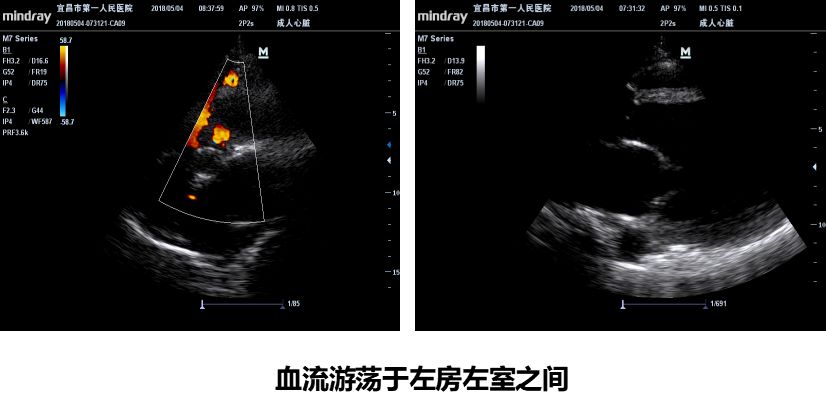

反复出现恶性心律失常:尖端扭转室速、室颤…

休克难以纠正:多巴胺、去甲肾、肾上腺素

强心治疗已没有空间:多巴酚、西地兰、米力农

心功能进一步恶化:LVEF进行性下降